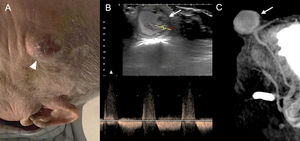

Traumatic pseudoaneurysm of the superficial temporal artery is rare. It usually develops as a painless pulsatile mass in the temporal region, often following blunt or penetrating craniocerebral injury. The time of onset is variable and is influenced by the nature of the lesion; it can appear 2−6 h after the trauma or weeks later22 (Fig. 13).

86-year-old man presenting with craniocerebral injury one month prior and since then a pulsatile mass in the left frontotemporal region of about 3 cm in diameter (arrowhead) (A). The ultrasound scan (B) shows an oval image arising from the left temporal artery with a sac with mobile internal echoes and turbulent flow consistent with a pseudoaneurysm of the left temporal artery (arrow), partially thrombosed and with bidirectional flow on spectral Doppler. The pseudoaneurysm can also be seen in the sagittal maximum intensity projection reconstruction of baseline brain CT (C).